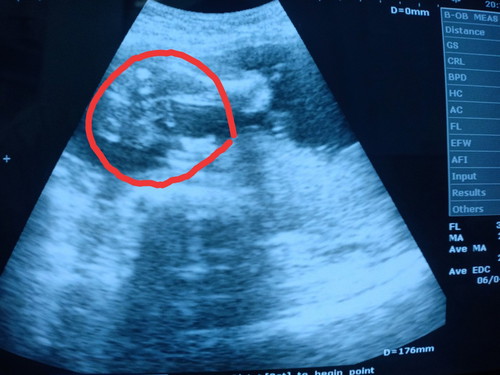

ทายกันหน่อยค่ะ

เป็นผู้ชายนะคะ.

น่าจะชาย

กำลังจะเป็นแม่